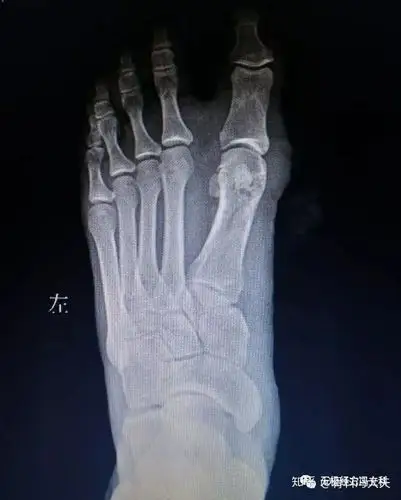

拇外翻的矫治

图片尺寸640x853